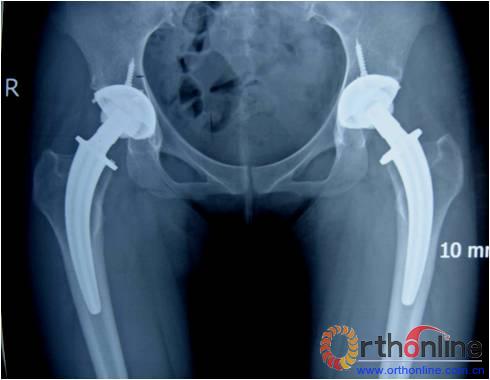

图1

图2

图3

图4

图5

图6

图为:方某,女,21岁,双侧激素性股骨头坏死,ARCO III-C期,C.F.P. 股骨假体THA前后双髋X线摄片。

图1、图2:术前;图3:术后;图4:术后3个月;图5:术后6个月;图6:术后1.2年